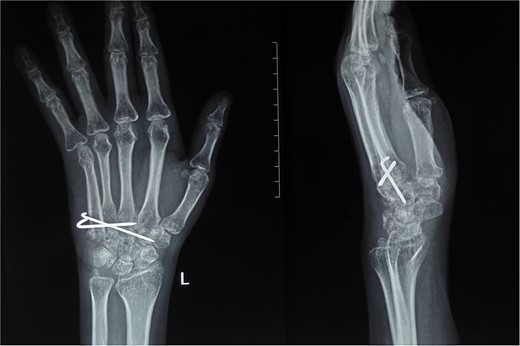

At 2 years postoperatively, the patient showed excellent functional outcomes. Radiographs demonstrated a stable MCP joint with well-preserved joint space, indicating successful graft incorporation (Fig. 3). Donor site radiographs at 2 years showed appropriate spacing between the third and fifth metatarsals with no evidence of arch collapse or stress reaction in the adjacent bones (Fig. 4). The patient achieved an active MCP joint range of motion of 0–80 deg (Fig. 5).

Post-operative radiograph showing preserved joint space and structure of transferred metatarsal.